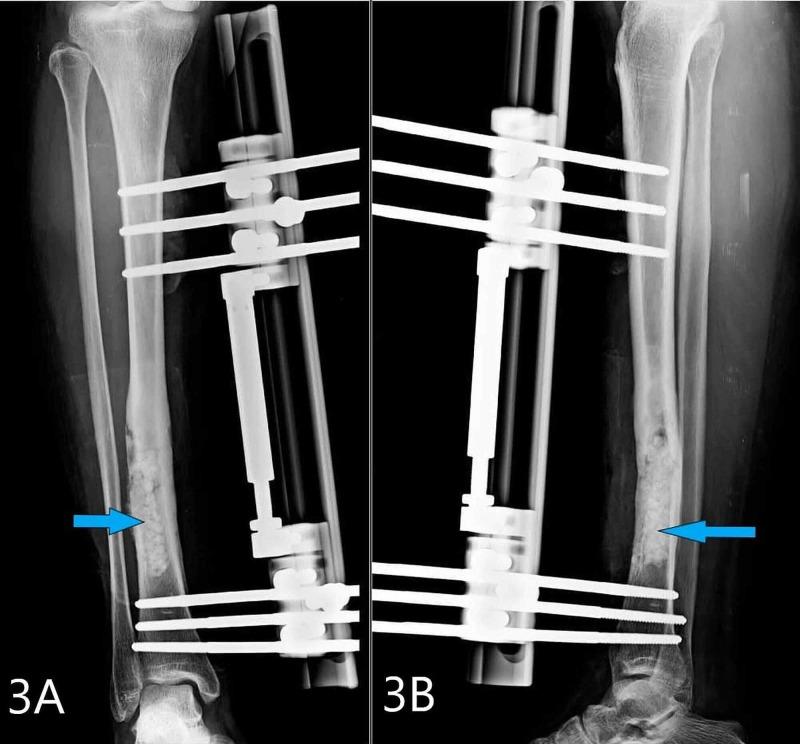

Salmonella osteomyelitis is usually seen in patients with hemoglobinopathies and immunodeficient individuals. However, it is a rare clinical entity in an immunocompetent person with very few cases reported in clinical literature usually caused by non-typhoid Salmonella. Here, we report a case of osteomyelitis of the right tibia in a 40-year-old immunocompetent lady. She developed a pathological fracture of the right tibia during the course of her treatment. It was then managed successfully by debridement and external fixation using a rail fixator. Salmonella osteomyelitis does not present with unique clinical or radiological signs. High index of suspicion with appropriate testing will help in determining the causative agent correctly and thus aid in its successful management.

沙门氏菌骨髓炎通常见于患有血红蛋白病的患者和免疫功能低下的个体。然而,在免疫功能正常的人中,这是一种罕见的临床病症,临床文献中报道的病例很少,通常由非伤寒沙门氏菌引起。在此,我们报告一例40岁免疫功能正常女性的右胫骨骨髓炎病例。她在治疗过程中发生了右胫骨病理性骨折。随后通过清创术和使用轨道固定器进行外固定成功治疗。沙门氏菌骨髓炎没有独特的临床或放射学征象。高度怀疑并进行适当检测将有助于正确确定病原体,从而有助于其成功治疗。